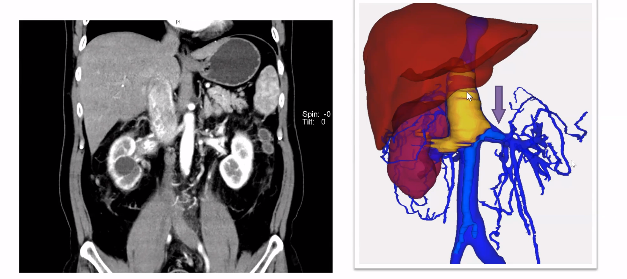

如下图所示,该病例瘤栓充满整个下腔静脉,同时长满血栓,对于该病例我们采用全封闭式的En-block切除,首先是离断下腔静脉,翻起来以后去找寻右肾动脉,切断右肾动脉以后再把左肾静脉切断,然后一直沿着瘤栓向肝后寻找游离肝门后方腔静脉。既往类似病例中肝门后方腔静脉很难暴露清楚,但是有了机器人助力,使其充分显露出来就变的相对容易很多。肝后下腔静脉经过充分游离后,再将瘤栓全部挤压进入腔静脉中,然后探查至无瘤栓处,直线切断腔静脉,将瘤栓取出。完全封闭式的瘤栓取出,可以获得很好的操作空间。该病例曾在2023年4月在第8届泌尿生殖系统研讨会上进行演示。